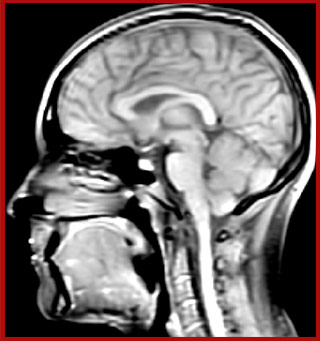

Juxtacortical MS lesion elition

Sagittal 3D FLAIR with 0.3 mm3 voxel volume acquired in 5:12 min. using Compressed SENSE showing a (juxta)cortical MS lesion.